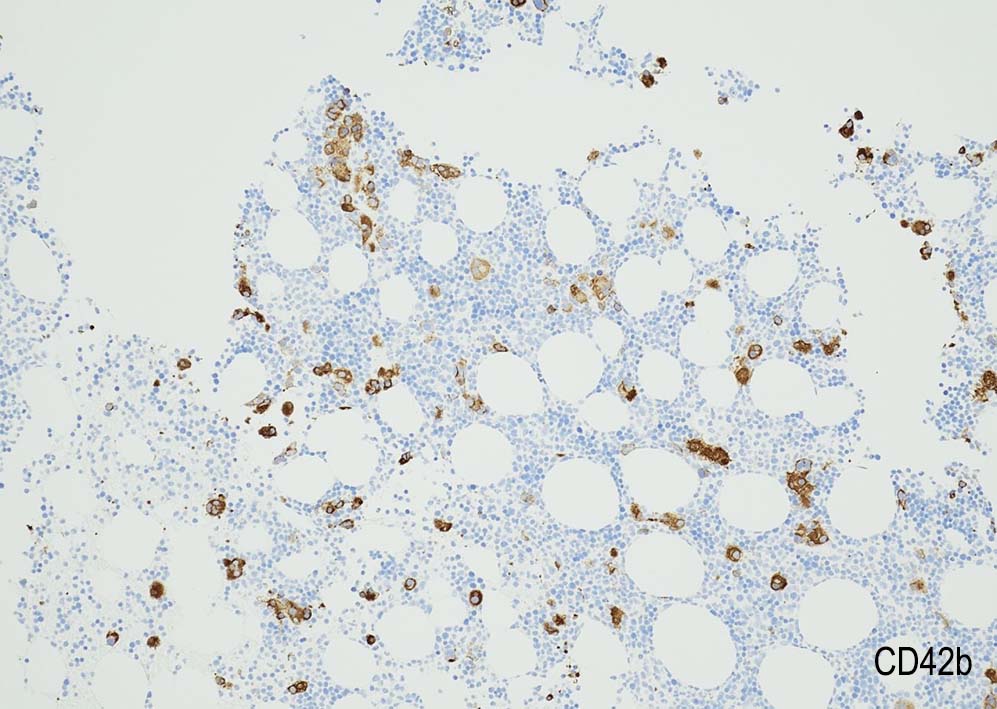

Megakaryopoiesis; Mgkは増加している. 多数の分離円形核巨核球が出現している. microMgkが増加している.